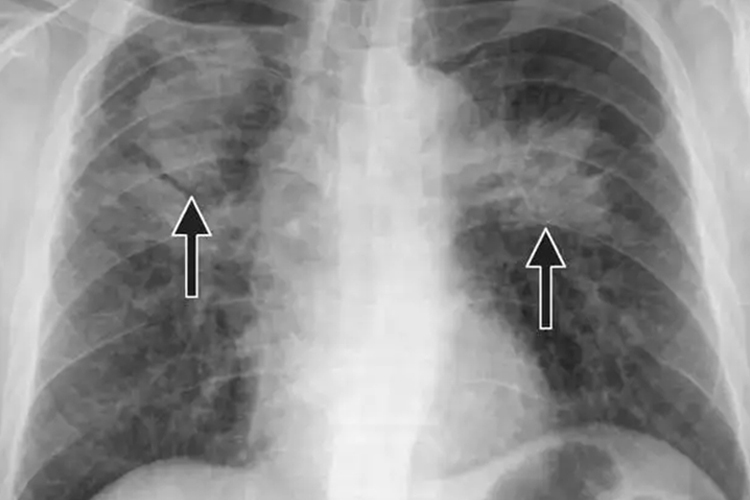

尘肺病典型X线表现为肺野有圆形小阴影,随病变发展小阴影逐渐增大、增多,密集度增高,分布范围也逐渐扩大乃至全肺,部分融合成大块状纤维。